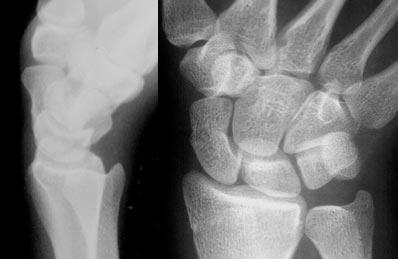

Ca lâm sàng 4

Phân tích:

Ca lâm sàng bên trái cho thấy thoái hóa khớp nặng tại khớp STT (thuyền-thang-thê) và khớp CMC1 (cổ tay-bàn tay ngón 1) kèm bán trật khớp. Các cung cổ tay bình thường và có tính song song bình thường. Xương thuyền bị kéo dài, cho thấy nó đang nghiêng ra phía sau (dorsally tilted).

Trên tư thế nghiêng, chúng ta có thể thấy xương nguyệt cũng nghiêng ra phía sau. Hàng cổ tay gần di chuyển như một khối thống nhất, do đó không có sự phân ly.

Chẩn đoán cuối cùng: DISI không phân ly (non-dissociated DISI) kèm thoái hóa khớp và bán trật khớp STT.